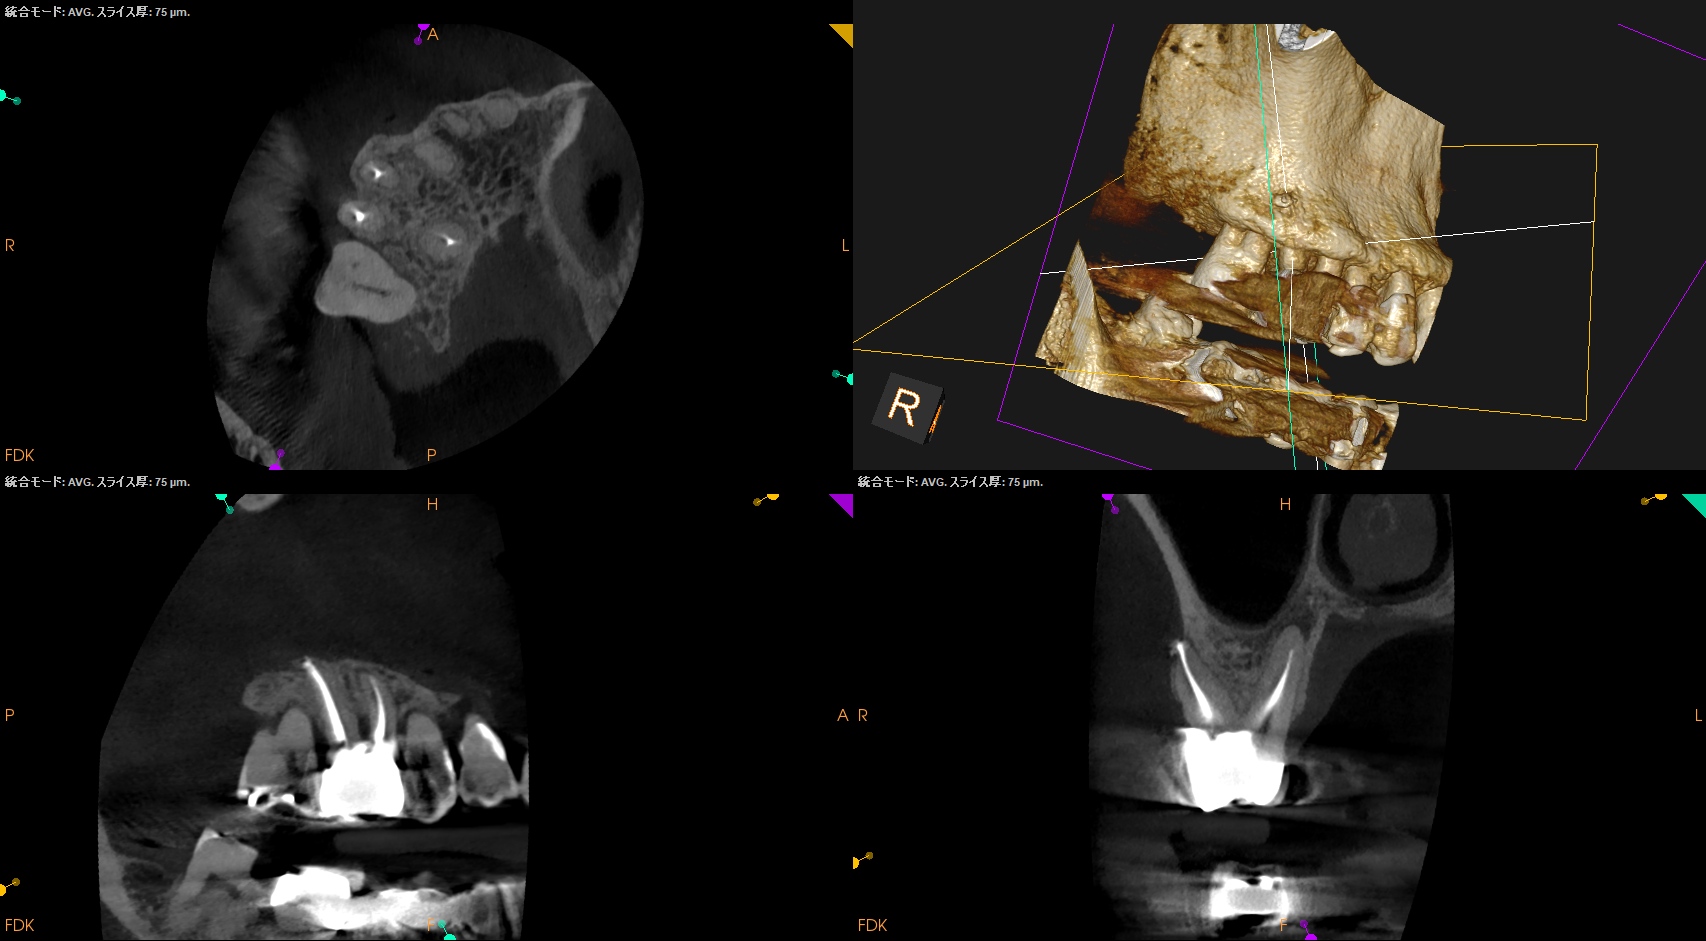

#3 RCT 1yr recall(2026.1.5)

DBの歯槽骨はまだ回復中(Healiing)だが臨床症状は消失した。

ということでまた来年も経過を見ることとなった。